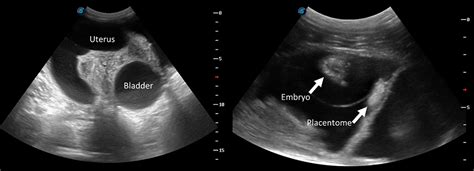

4. Ultrasound: An ultrasound can confirm or rule out pregnancy by visualizing the uterus and ovaries. This is a very helpful tool in providing a clear answer to confirm. It can also help identify any underlying medical conditions, such as ovarian cysts or uterine fibroids.